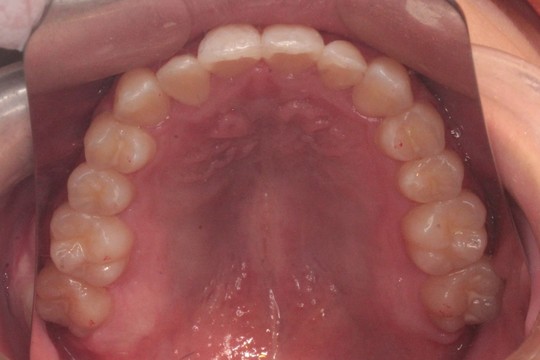

治療前

治療後

治療前後写真について

調布市の20代男性

主訴:歯並びをきれいにしたい

使用装置:インビザライン

治療期間:約3年

治療費用:93.5万円(税込)

治療結果:交叉咬合と叢生が改善されました